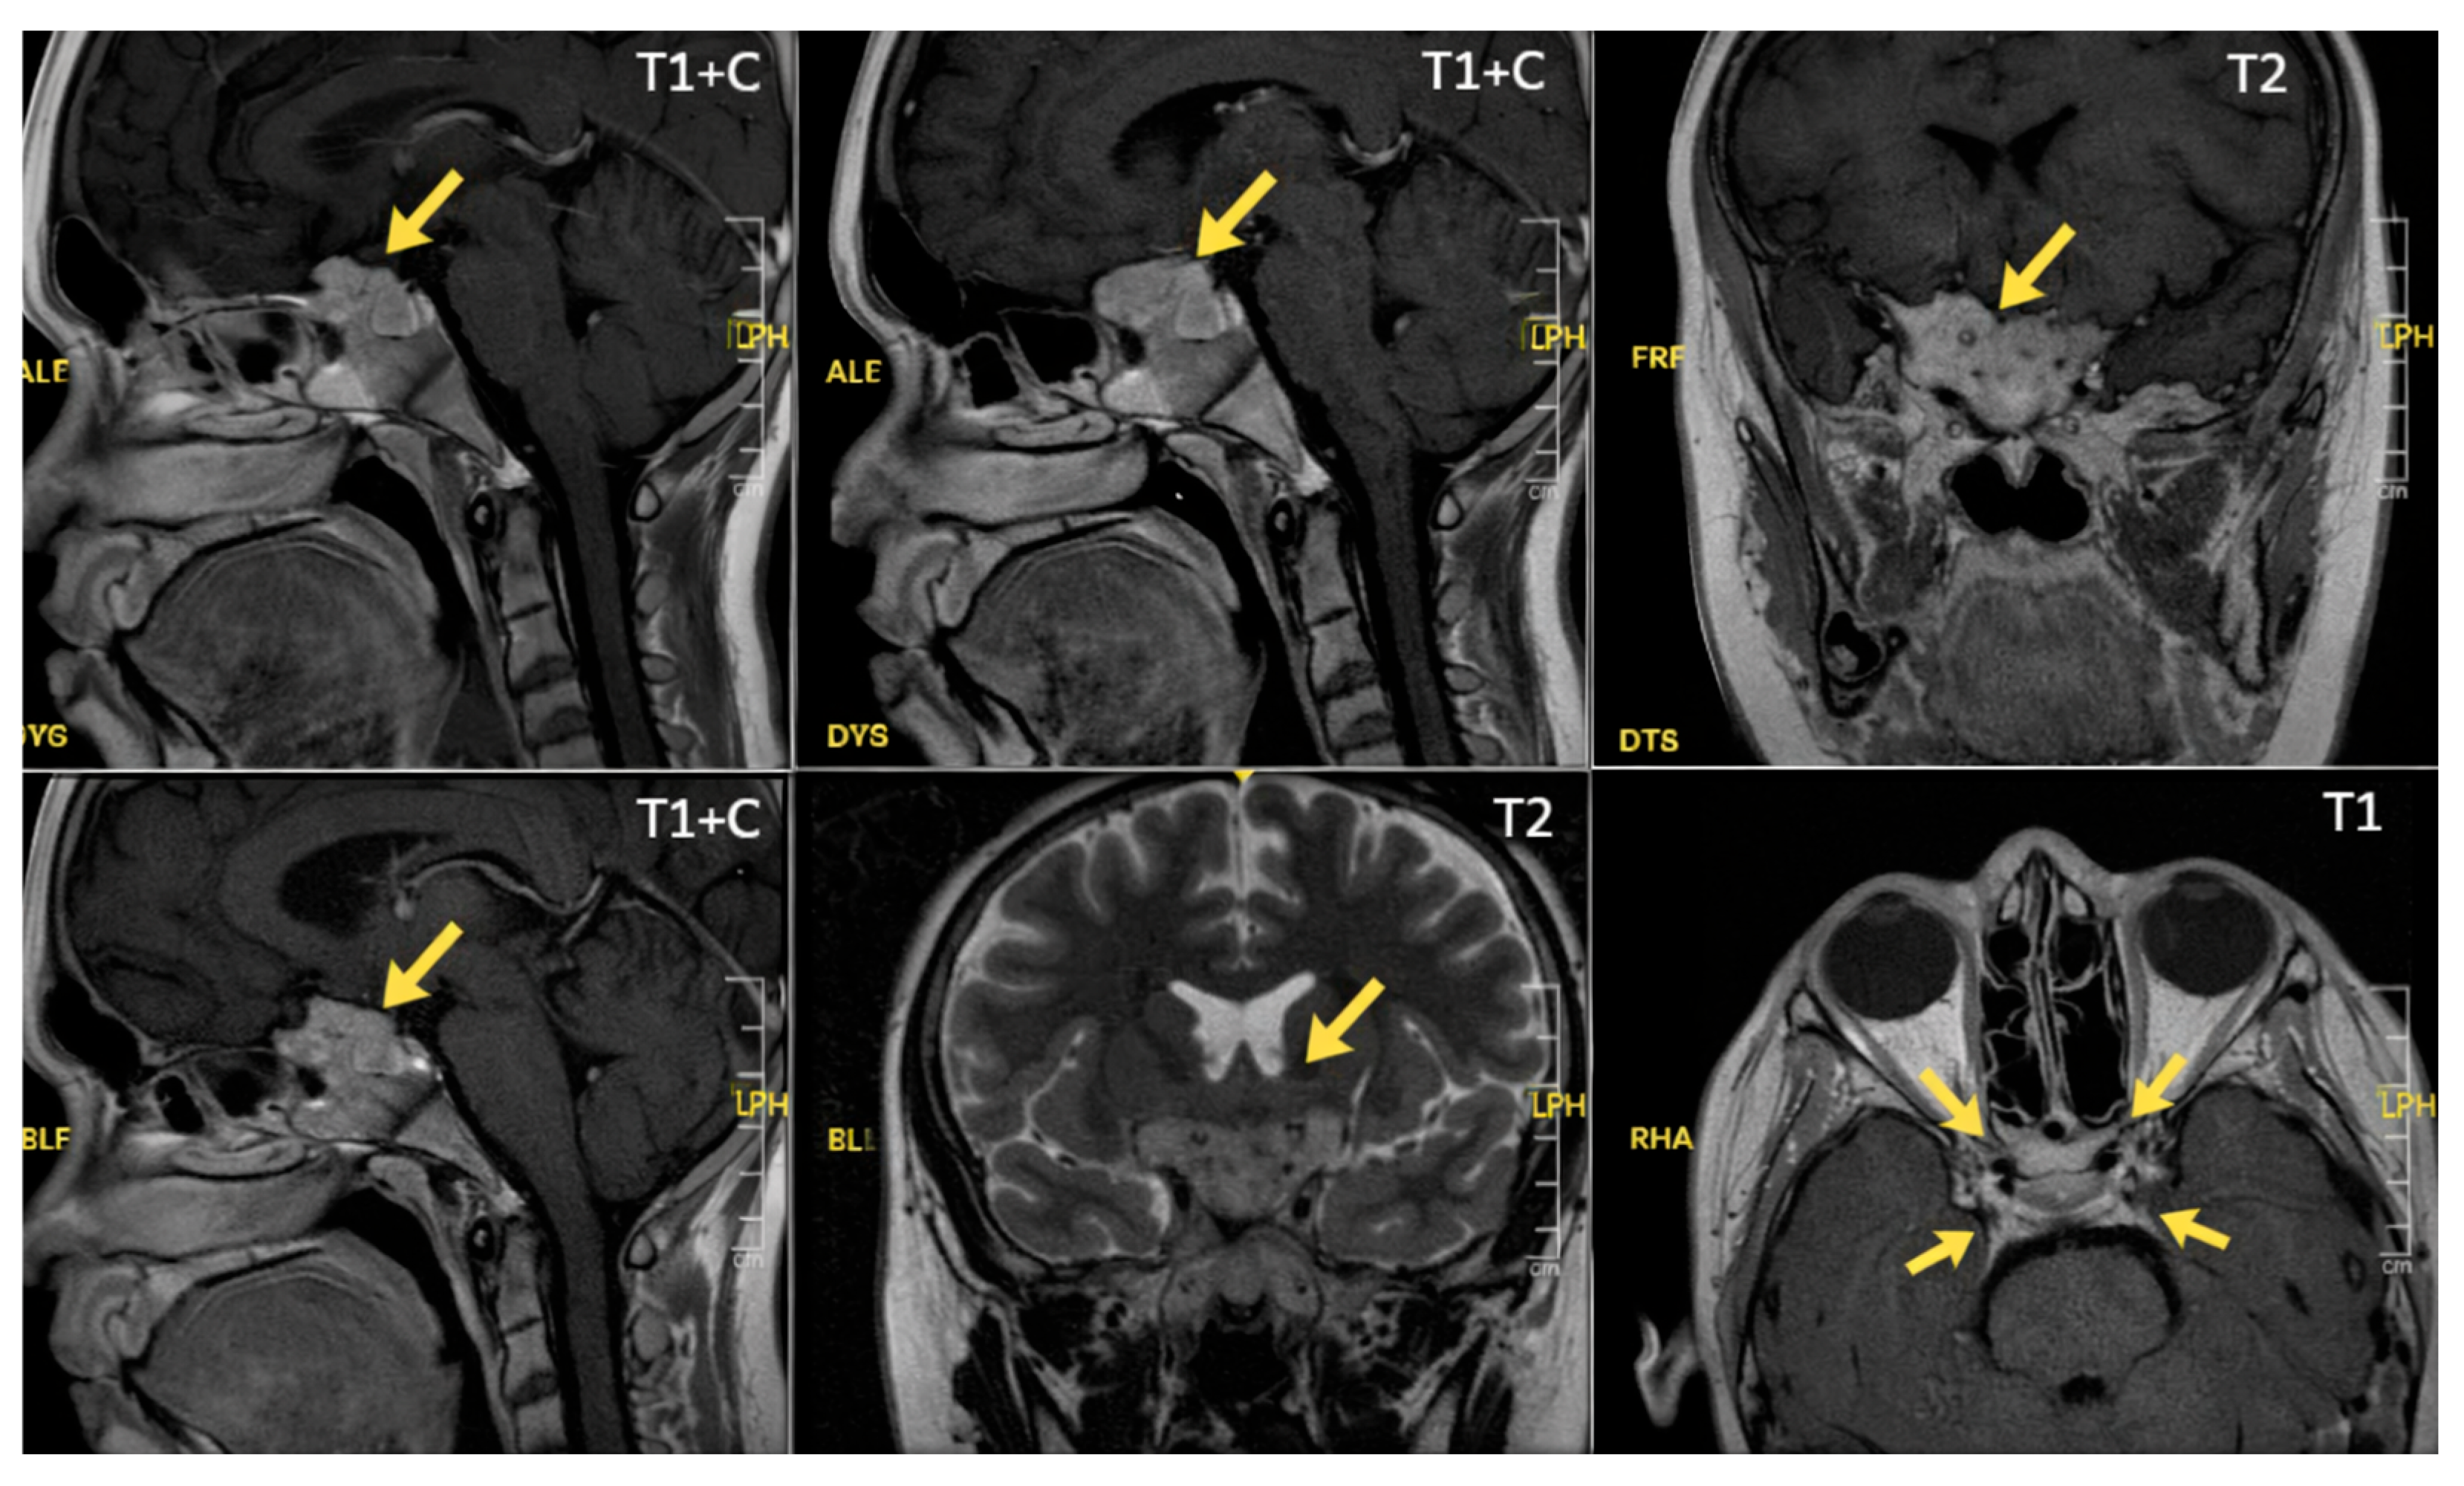

2. Case Presentation

2.2. Clinical Findings